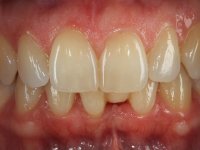

Case 2: clinical

Female patient, 40 years old, non-smoker. Presented agenesis of tooth 31 with the presence of deciduous tooth 71.

After clinical and radiographic examination, two alternatives for the oral rehabilitation were proposed:

• orthodontic treatment to open the mesio-distal space to allow the placement of a dental implant and its crown;

• ‘Maryland bridge’, with a slight slice of adjacent teeth to allow the creation of a pontic with a mesio-distal diameter compatible with adjacent teeth.

Patient chose the second option.